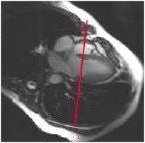

2. From the 2-chamber view, prescribe (yellow line indicates graphic location) and acquire a 4-chamber view.

Figure 2. Prescribe 4-chamber view